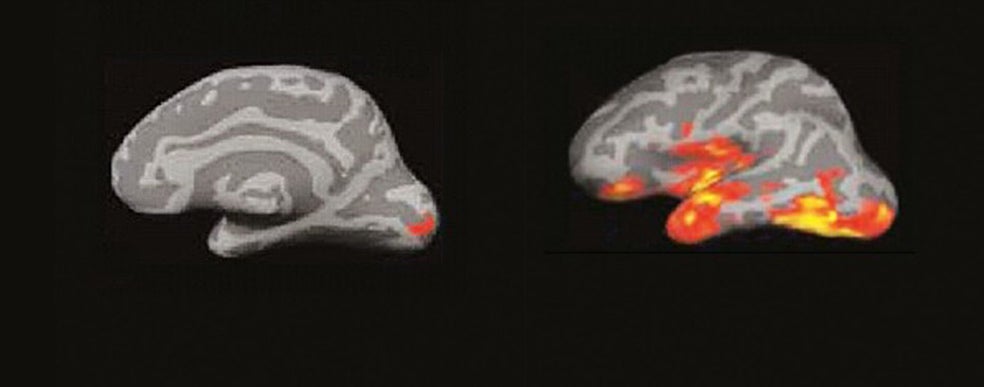

Para muchas personas, el tacto de las páginas o el peso del ejemplar entre las manos es una parte irrenunciable de la experiencia lectora. No hay e-book, tableta ni smartphone que puedan sustituir esa sensación. Pero son una minoría. Según el último barómetro de hábitos de lectura, publicado en 2018 por la Federación de Editores, solo el 40 por ciento de los lectores lee exclusivamente en papel. En realidad, los datos no hacen más que confirmar nuestros propios hábitos. Pero más allá del impacto que el libro digital ha tenido en el negocio editorial, pocos se han parado a pensar en cómo afecta a nuestra capacidad lectora el soporte que elegimos para disfrutar de una novela, un ensayo o un libro de autoayuda. Una de ellas es la neurocientífica cognitiva Maryanne Wolf, especialista en el cerebro lector y profesora de la Universidad de California en Los Ángeles, donde dirige el Centro de Dislexia, Estudiantes Diversos y Justicia Social. Autora de más de 170 artículos académicos y del superventas Cómo aprendemos a leer, su último libro es Lector, vuelve a casa: cómo afecta a nuestro cerebro la lectura en pantallas (Deusto Ediciones). Escrito como una compilación de cartas dirigidas a sus lectores, Wolf reflexiona sobre el impacto que las pantallas están teniendo en la lectura profunda, el análisis crítico y hasta en nuestra capacidad para empatizar con el prójimo. Pero también en el futuro de nuestras democracias…